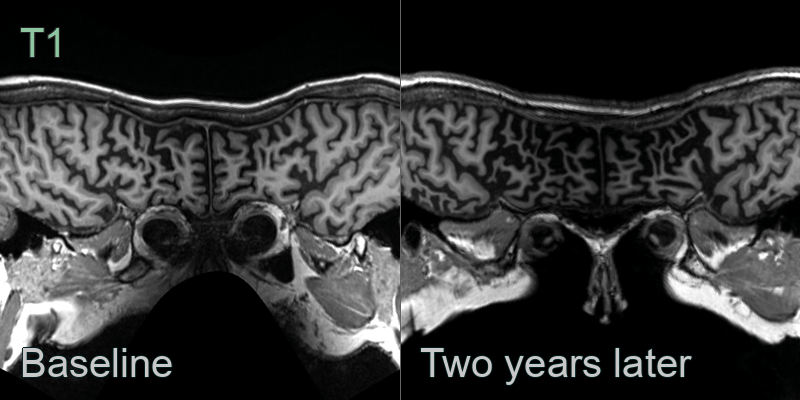

- A 60-year-old patient presented with disinhibition and impaired naming and verbal memory.

- MRI showed pronounced anterior temporal, milder left parietal, and no frontal lobe atrophy. There was particularly pronounced atrophy of the amygdalae.

- CSF amyloid markers were normal, making Alzheimer's disease unlikely. Genetic testing revealed a MAPT mutuation as the cause of frontotemporal dementia.